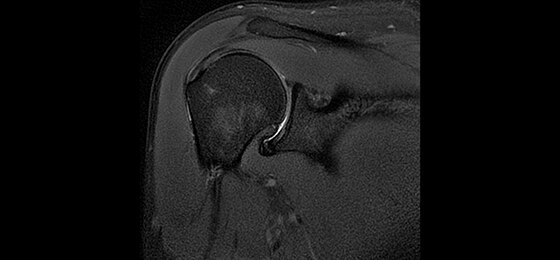

A large usable field of view is needed to properly image off-center anatomy such as a shoulder or hip. So the Discovery* MR750w features a 70 cm flared, open bore design with a large 50 x 50 x 50 cm field of view.

Gradients and RF body coils are water and air-cooled for optimum duty-cycle performance, short repetition time (TR) and echo time (TE), producing sharp and clear images.